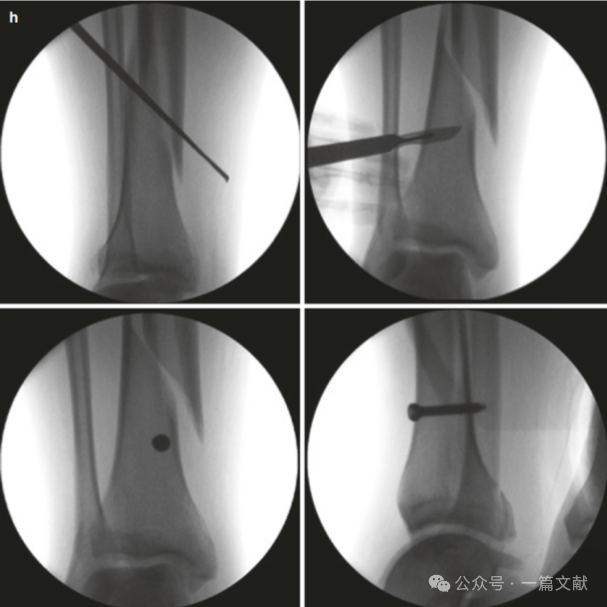

随后的阻挡螺钉被置入在髓内钉的另一侧,即拇指和手指放置在骨头上的相反侧(按压的对侧)。如下图:本例展示了仅在远端骨块(干骺端)打入两枚阻挡钉,首先在靠近骨折线的近端打入一枚阻挡钉,不足以完全纠正畸形,随后在远端骨块髓内钉对侧的远端打入第二枚阻挡钉。

2,阻挡钉离中线和骨折线的距离目前尚无定论,一般推荐离骨折线约1-3cm,离中线越近越安全(6-7mm)。具体根据骨折形态和髓内钉直径而定,离骨折线太近易造成继发骨折,离中线太近则可能阻碍主钉置入,太远又可能无复位效果,如下图: